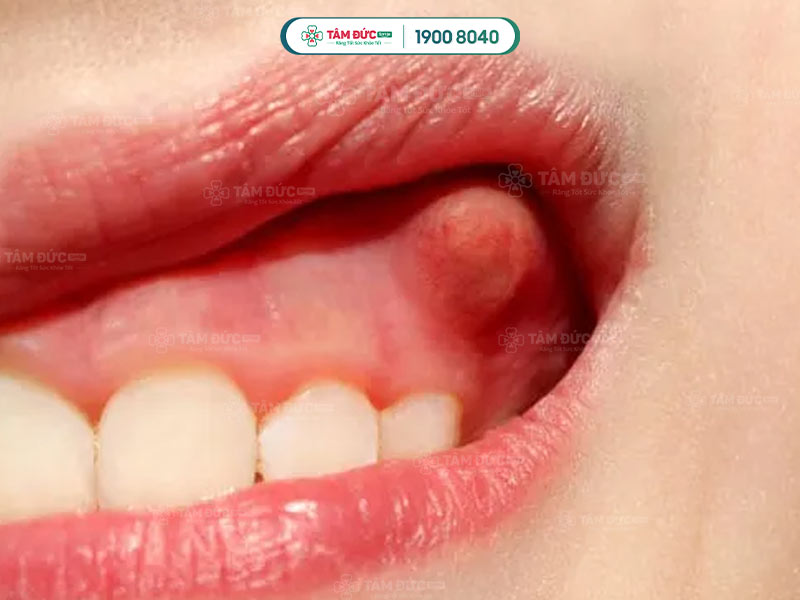

1.2.1. Áp xe nướu

- Xuất hiện khi vi khuẩn gây nhiễm trùng giữa nướu và răng.

- Thường do các mảnh thức ăn hoặc răng chưa mọc bị mắc kẹt trong túi nướu.

- Dấu hiệu nhận biết áp xe nướu: sưng, đau trên vùng nướu.

Áp xe nướu răng